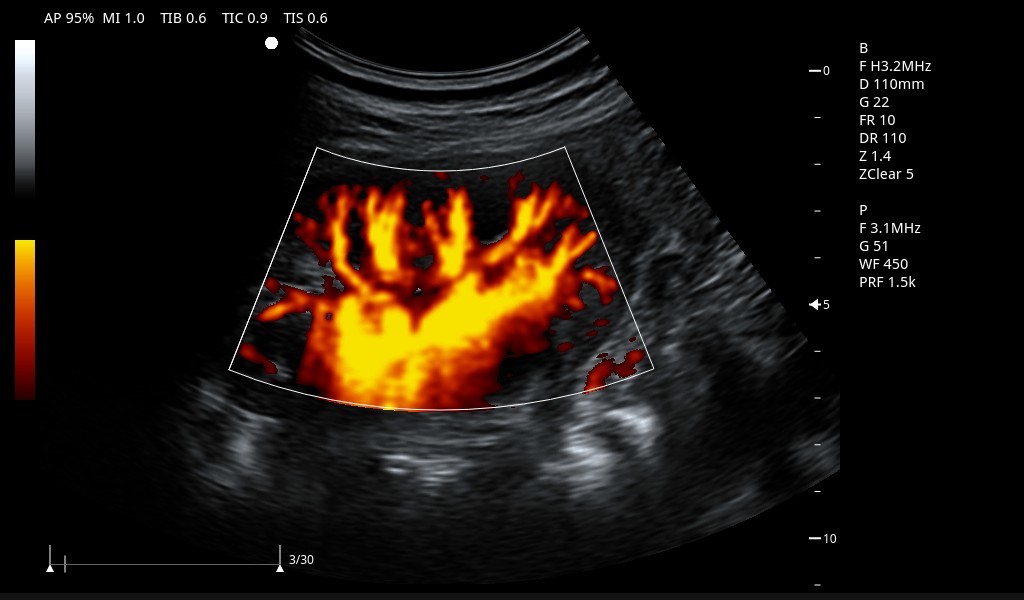

Excelentes imágenes clínicas

|

|

|

|

|

|